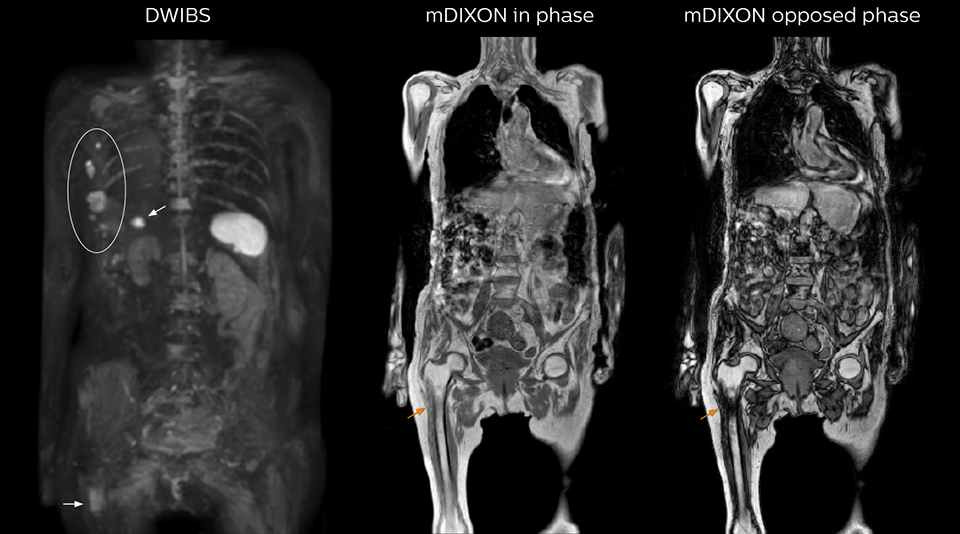

“The DWIBS sequence’s value in oncology cases is due to the high contrast it creates between lesions and surrounding tissue. Whole body DWI is requested by physicians who need to clarify TNM staging or determine therapeutic strategies, oncologists in need of diagnosis or follow-up scans, surgeons who need to see the presence of distant lesions that are sometimes difficult to detect by CT before surgery, and urologists for the evaluation of bone lesions, and the effect of chemotherapy and radiotherapy.”

“mDIXON FFE allows us to quickly get information we need to assess the presence of fat. That gives us more information when we need to diagnose bone lesions, and when we are asked to judge fat-containing lesions such as hepatocellular or renal carcinoma,” Dr. Nobusawa says. “The mDIXON fat images can help us to differentiate fatty bone marrow from bone lesions. This is especially useful in elderly people, who tend to have fattier bone marrow. The water images provide a high signal-to-noise ratio in the intestinal canal, which is valuable for visualizing lesions in the colon,” he says.

Kawasaki Sawai Hospital’s whole body protocol also includes an mDIXON FFE sequence. Because mDIXON provides images for four contrast types – water only, fat only, in-phase and out-of-phase – from a single acquisition, it is useful in many ways.

“In-phase and out-phase sagittal T1-weighted FFE images help us to visualize and further characterize bone lesions such as metastasis and bone-marrow hyperplasia that have high signal on DWI. These images are also used throughout radiotherapy, to monitor changes in the fatty bone marrow.”

After implementing the improved whole body protocol, the radiology team initially did not see a large increase in referrals, although Dr. Nobusawa saw clinical cases where the DWIBS images provided him valuable information for diagnosis. This is why Dr. Nobusawa and Mr. Naka started to actively educate referring physicians about the value of whole body DWIBS. They organized several presentations for physicians in the hospital, where they explained how DWIBS can be of value in oncology patients. The information it provides can be useful for physicians when staging cancer, as well as when determining or adjusting treatment strategy. Mr. Naka remembers some cases where DWIBS provided remarkable information. “In one example, DWIBS visualized bone lesions that could not be seen on PET or SPECT. In another case we had found a bone lesion when a normal L-spine scan for narrowing of the disk space was done. One extra DWIBS scan (2 stations, 8 minutes) demonstrated a lesion that later was confirmed to be the primary region of cancer.”